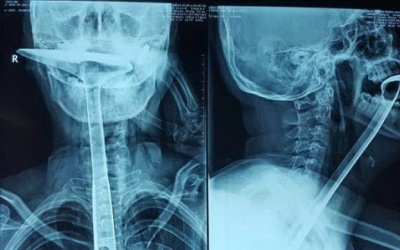

Cảm thấy khó thở, người phụ nữ 31 tuổi cố gắng thông cổ họng bằng ngón tay, chiếc đũa và xẻng nấu ăn dài 30 cm.